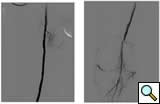

![]() |

|

Figure 1A: Angiogram |

Figure 1B: Following a day |

| Figure 1C: Angiogram shows restoration of limb perfusion. |

Case 1: An 84-year-old male with rest pain, who had undergone prior revascularization with covered stents, represents with recurrent rest pain. The prior stents had come close to the origin of the SFA and at that time there had been some narrowing. Exposure was provided by performing a cut down and patching the CFA-proximal SFA to the level of the stents, following which gentle thrombectomy was performed, and a wire passed down. The angiogram demonstrated a distal lesion at the adductor canal which contributed to the thrombosis (Figure 1A). The patient underwent a day of lysis, following which cryoablation was used to treat the distal lesion (Figure 1B) and completion angiogram showed restoration of limb perfusion (Figure 1C).